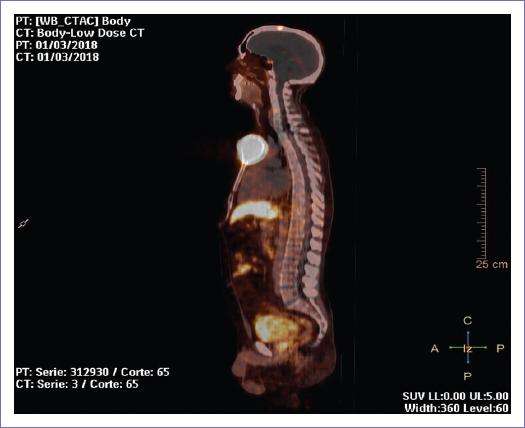

Cerca del 90% de los feocromocitomas y paragangliomas metastásicos presentan una notable expresión de receptores de somatostatina. Esta característica biológica permite que estos tumores sean identificados mediante la tomografía por emisión de positrones con 64Cu-DOTATATE, una técnica de imagen que se aprovecha de la afinidad de los tumores por estos receptores. La visualización de estos tumores mediante 64Cu-DOTATATE-PET permite un diagnóstico preciso y, lo más importante, facilita el uso de tratamientos con análogos de somatostatina. Estos fármacos, que imitan la acción de la somatostatina, pueden ser empleados para reducir la proliferación tumoral y controlar los síntomas relacionados, como la hipertensión, que es frecuente en pacientes con tumores secretorios de catecolaminas. El tratamiento con análogos de somatostatina se puede probar en aquellos pacientes cuya enfermedad presenta estas características, con el objetivo de evaluar su efectividad en la reducción del crecimiento tumoral.

La terapia con radioisótopos dirigidos a tumores ha cobrado importancia en el tratamiento de los feocromocitomas y paragangliomas metastásicos. Uno de los tratamientos más utilizados es el 131I-iobenguane, una forma de radioterapia dirigida que emplea el radioisótopo I-131 para atacar los tumores que presentan una captación significativa de 123I-MIBG en imágenes diagnósticas. Aproximadamente el 60% de los pacientes con estos tumores metastásicos tienen suficiente captación de MIBG para beneficiarse de este tratamiento con 131I-MIBG de alta actividad específica. Este tratamiento ha sido aprobado por la FDA bajo la marca Azedra (iobenguane I-131) y ha mostrado eficacia en la mejora de los marcadores tumorales, así como en la reducción de la hipertensión y otros síntomas derivados de la secreción excesiva de catecolaminas. No obstante, aunque algunos pacientes experimentan remisiones duraderas, la mayoría finalmente experimenta progresión de la enfermedad.

Otra opción de tratamiento con radioisótopos es la terapia con radionúclidos acoplados a receptores de péptidos, también conocida como tratamiento con análogos de somatostatina marcados con radionúclidos. Un ejemplo es el 177Lu-DOTATATE (Lutathera), que está aprobado por la FDA para el tratamiento de tumores neuroendocrinos gastroenteropancreáticos metastásicos. Sin embargo, este tratamiento también se está utilizando de manera no oficial (off-label) para pacientes con feocromocitoma y paraganglioma metastásico, ya que el 90% de estos tumores son muy sensibles a la terapia con radionúclidos. El índice de respuesta objetiva es del 25%, y la tasa de control de la enfermedad a corto plazo alcanza el 84%, lo que indica que esta terapia puede ofrecer un control efectivo en el manejo de estos tumores metastásicos.